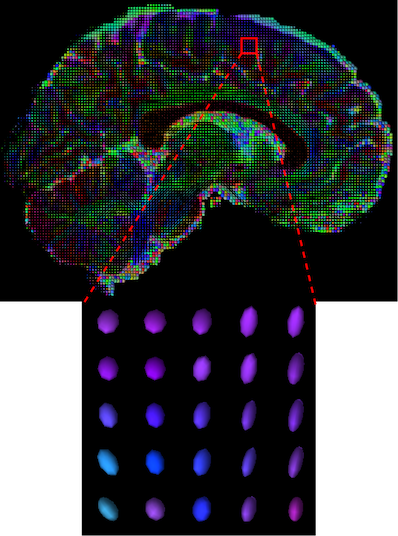

The visualization of inpainted results (showing the whole diffusion tensor for each voxel) generated from different models are demonstrated in Figure 3, where the tensor is represented in RGB coding that colours red, green and blue represent diffusion in the x, y, and z axes respectively. One typical example of reconstruction in the disrupted ROIs has been zoomed for visualization. Compared to the ground truth, TW-BAG is able to generate more distinct orientations following the original distribution and intensity across sagittal, coronal and axial views, which could demonstrate water diffusivity (denoted by eigenvalues of tensor model) more accurately. As indicated in Figure 4, the boundaries and textures of the FA map for TW-BAG are less blurry than the other competing models, validating the effectiveness of TW-BAG from a neuroscience perspective.